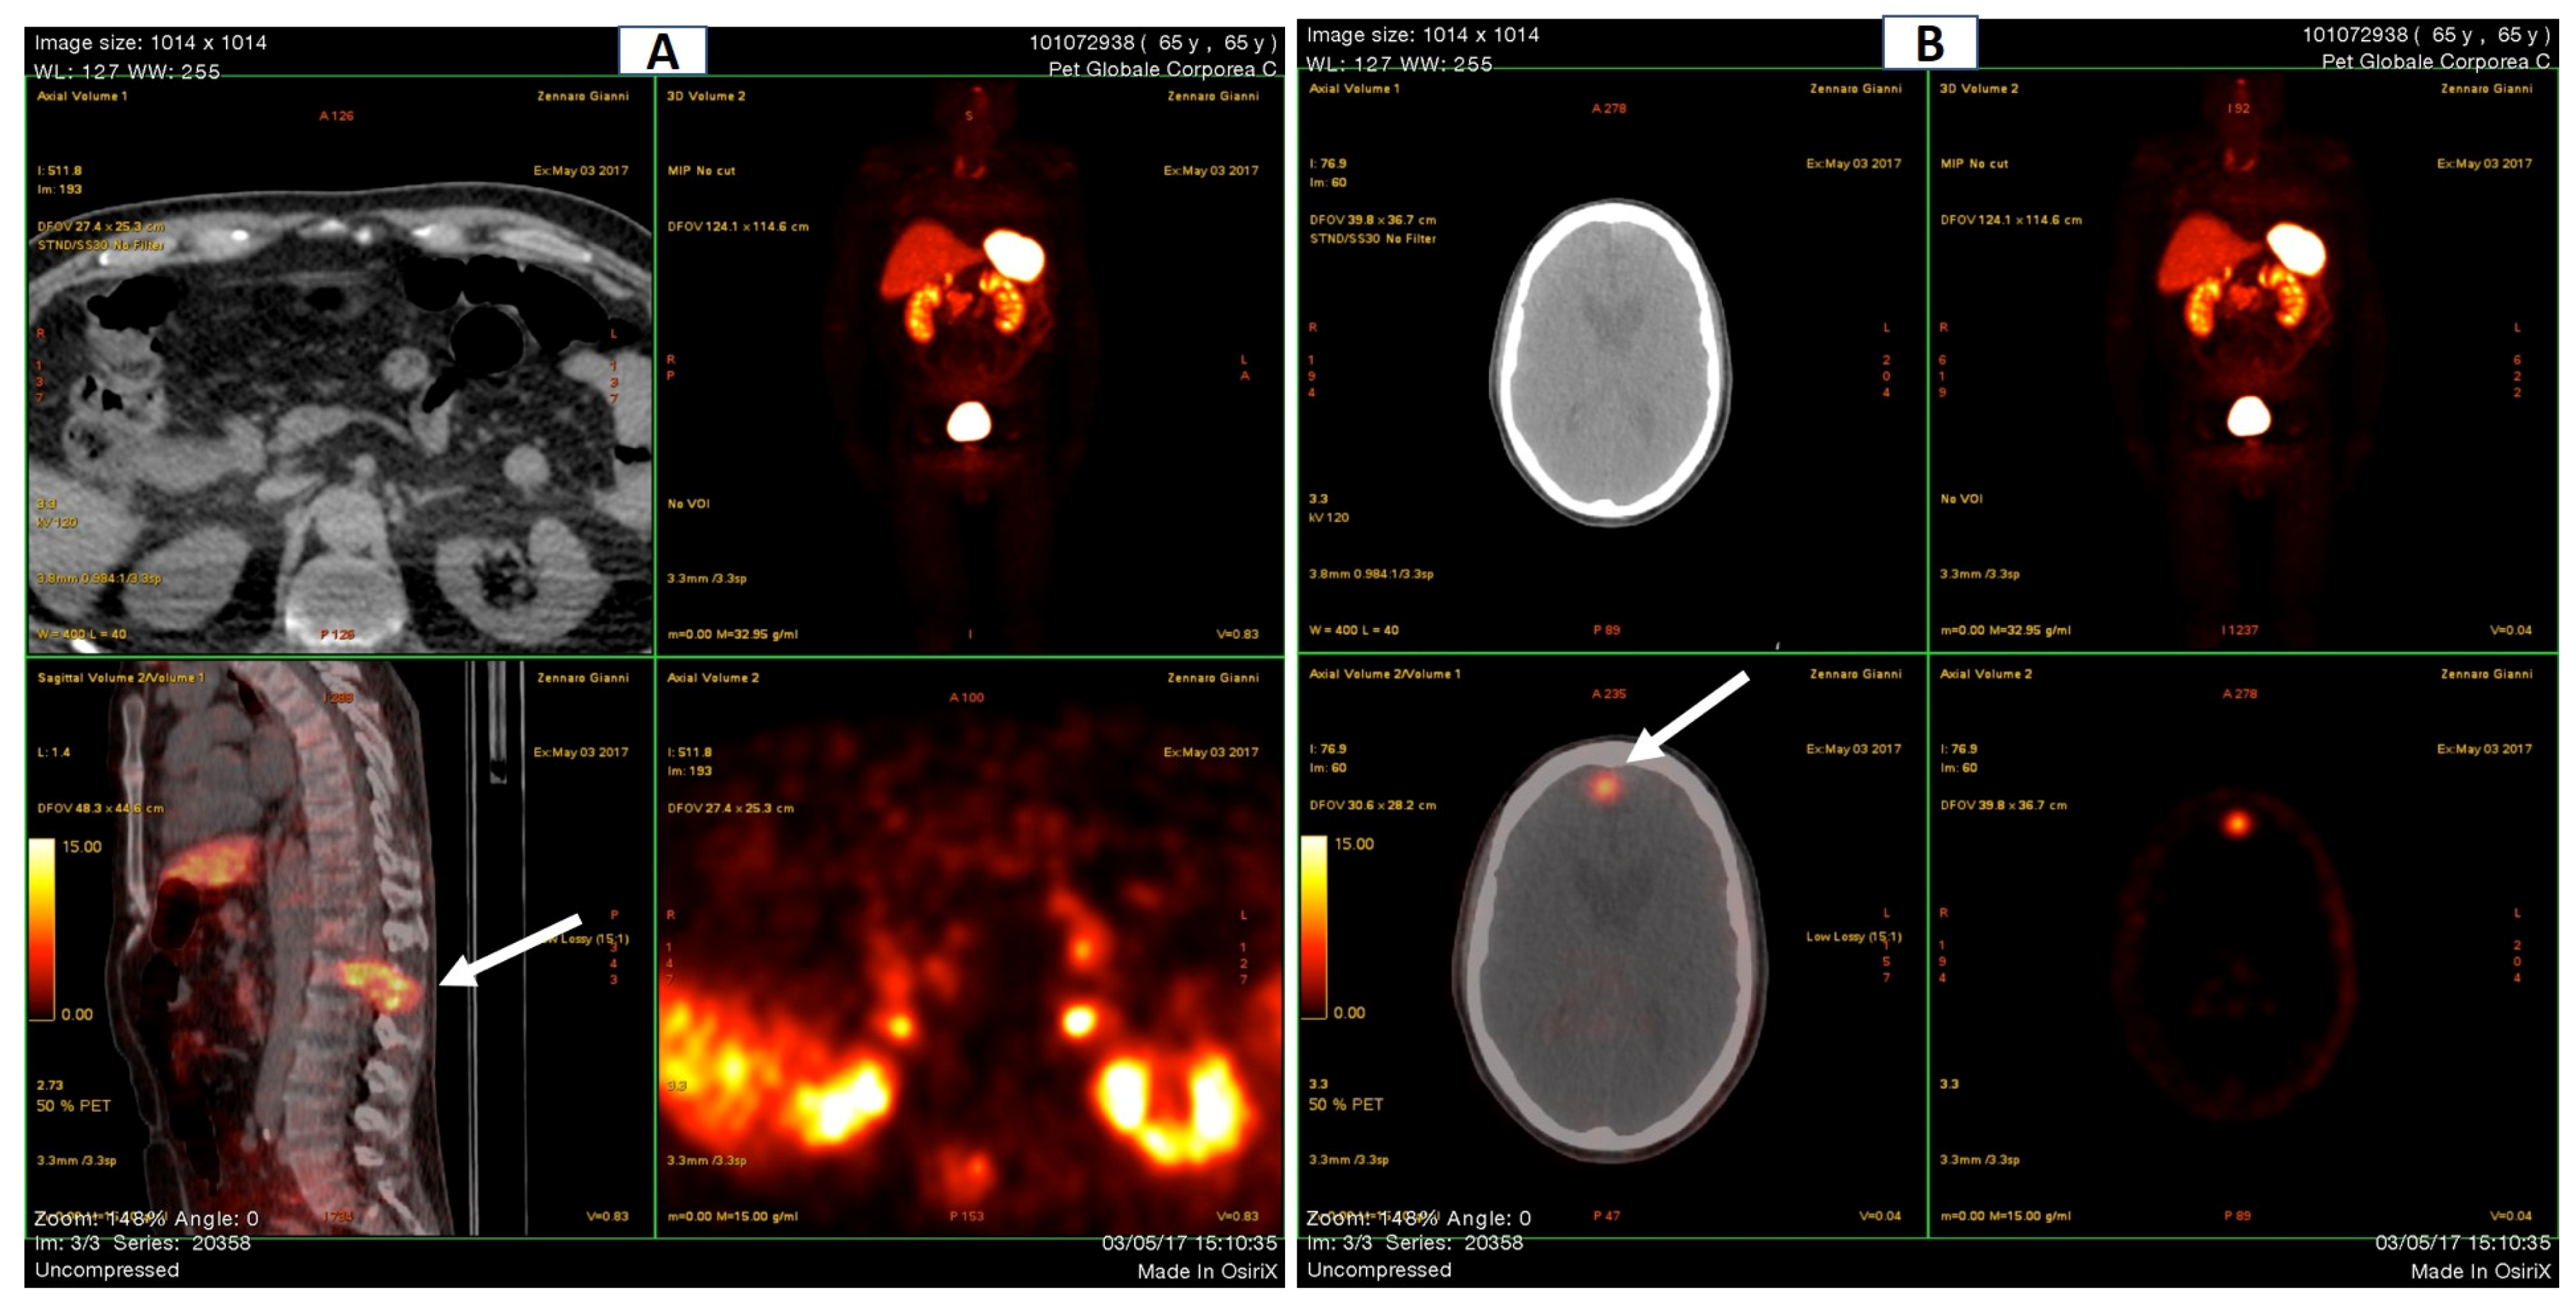

Total body scintigraphy revealed hypercaptation of rib-costal joints with a marked rosary sign at the chest, and some other mildly captating regions (Figure 1).

Figure 1. Total body scintigraphy (September 2015). (A) Front view. A Marked rosary sign at the chest. (B) Back view. Non-homogeneous spinal distribution of the tracer with increased uptake at the dorso-lumbar junction.